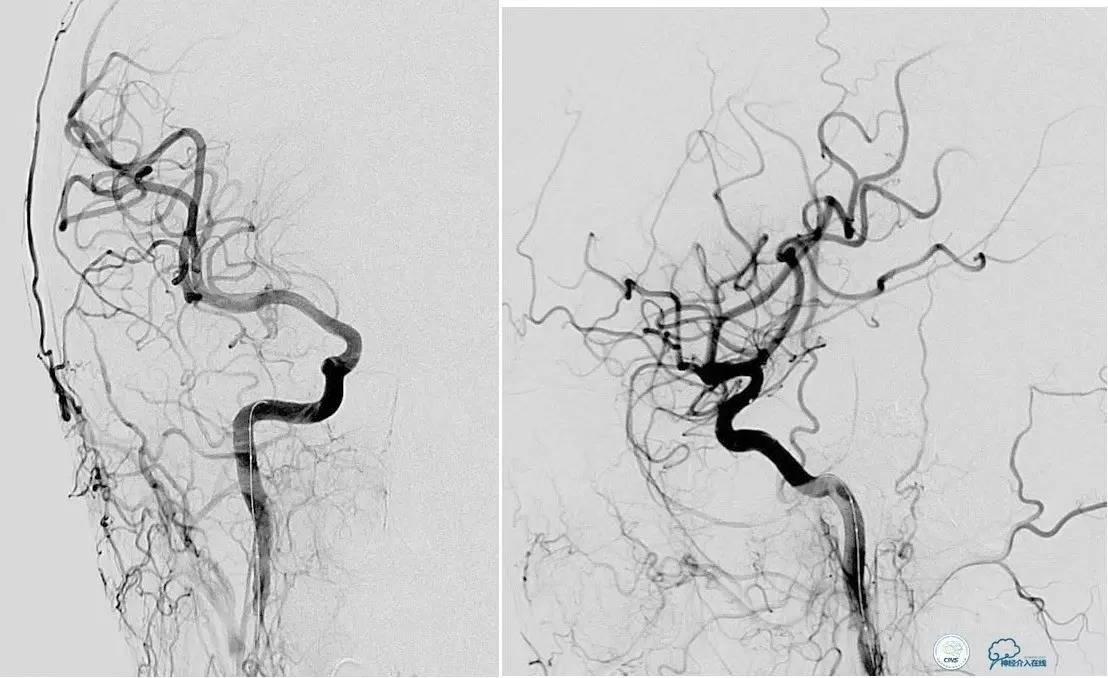

海绵窦区DAVF,颈内外均参与供血。

采用净买入路,经岩下窦栓塞。

首先放入少量弹簧圈,给Onyx提供框架。

开始注入Onyx时,在颈内动脉内放入保护球囊,防止意外进入颈内动脉内。

栓塞后胶的透视影像。

最终结果,DAVF完全消失。